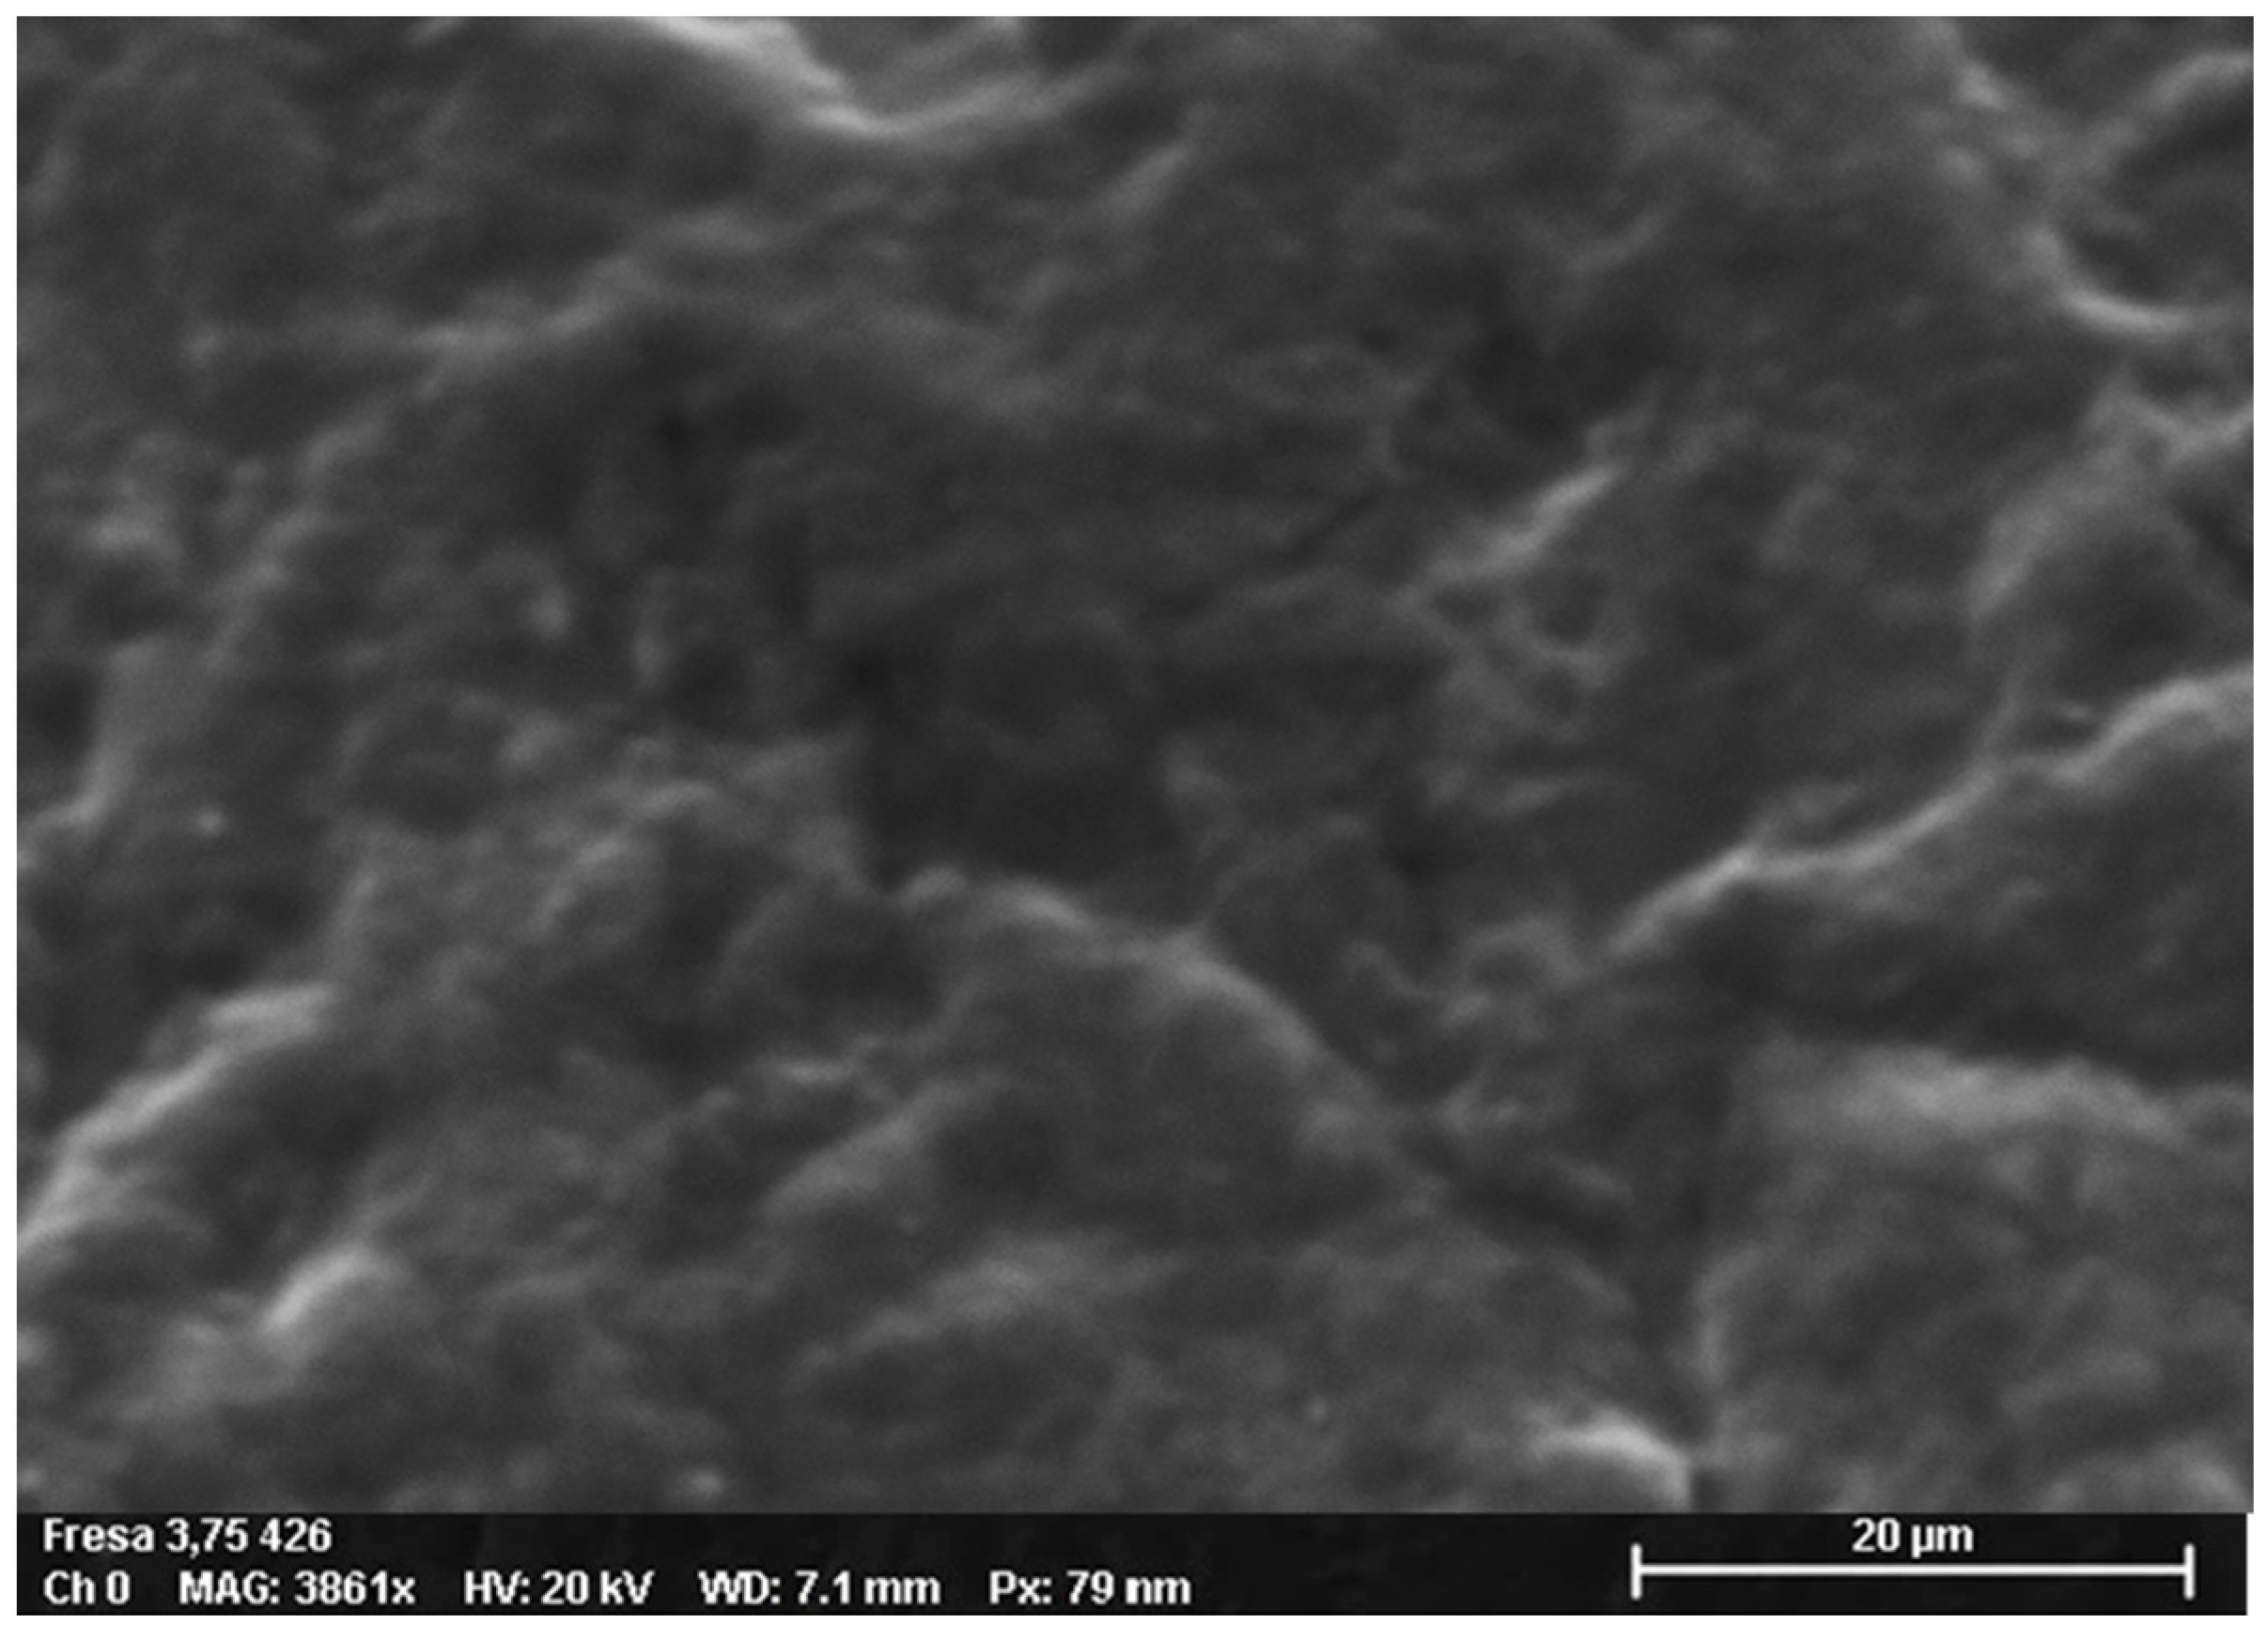

3.2. Scanning Electron Microscopy-EDS Analysis

3.2.1. Non-Sterilized Drill and Conical Tapper

3.2.2. Used and Sterilized Drill and Conical Tapper